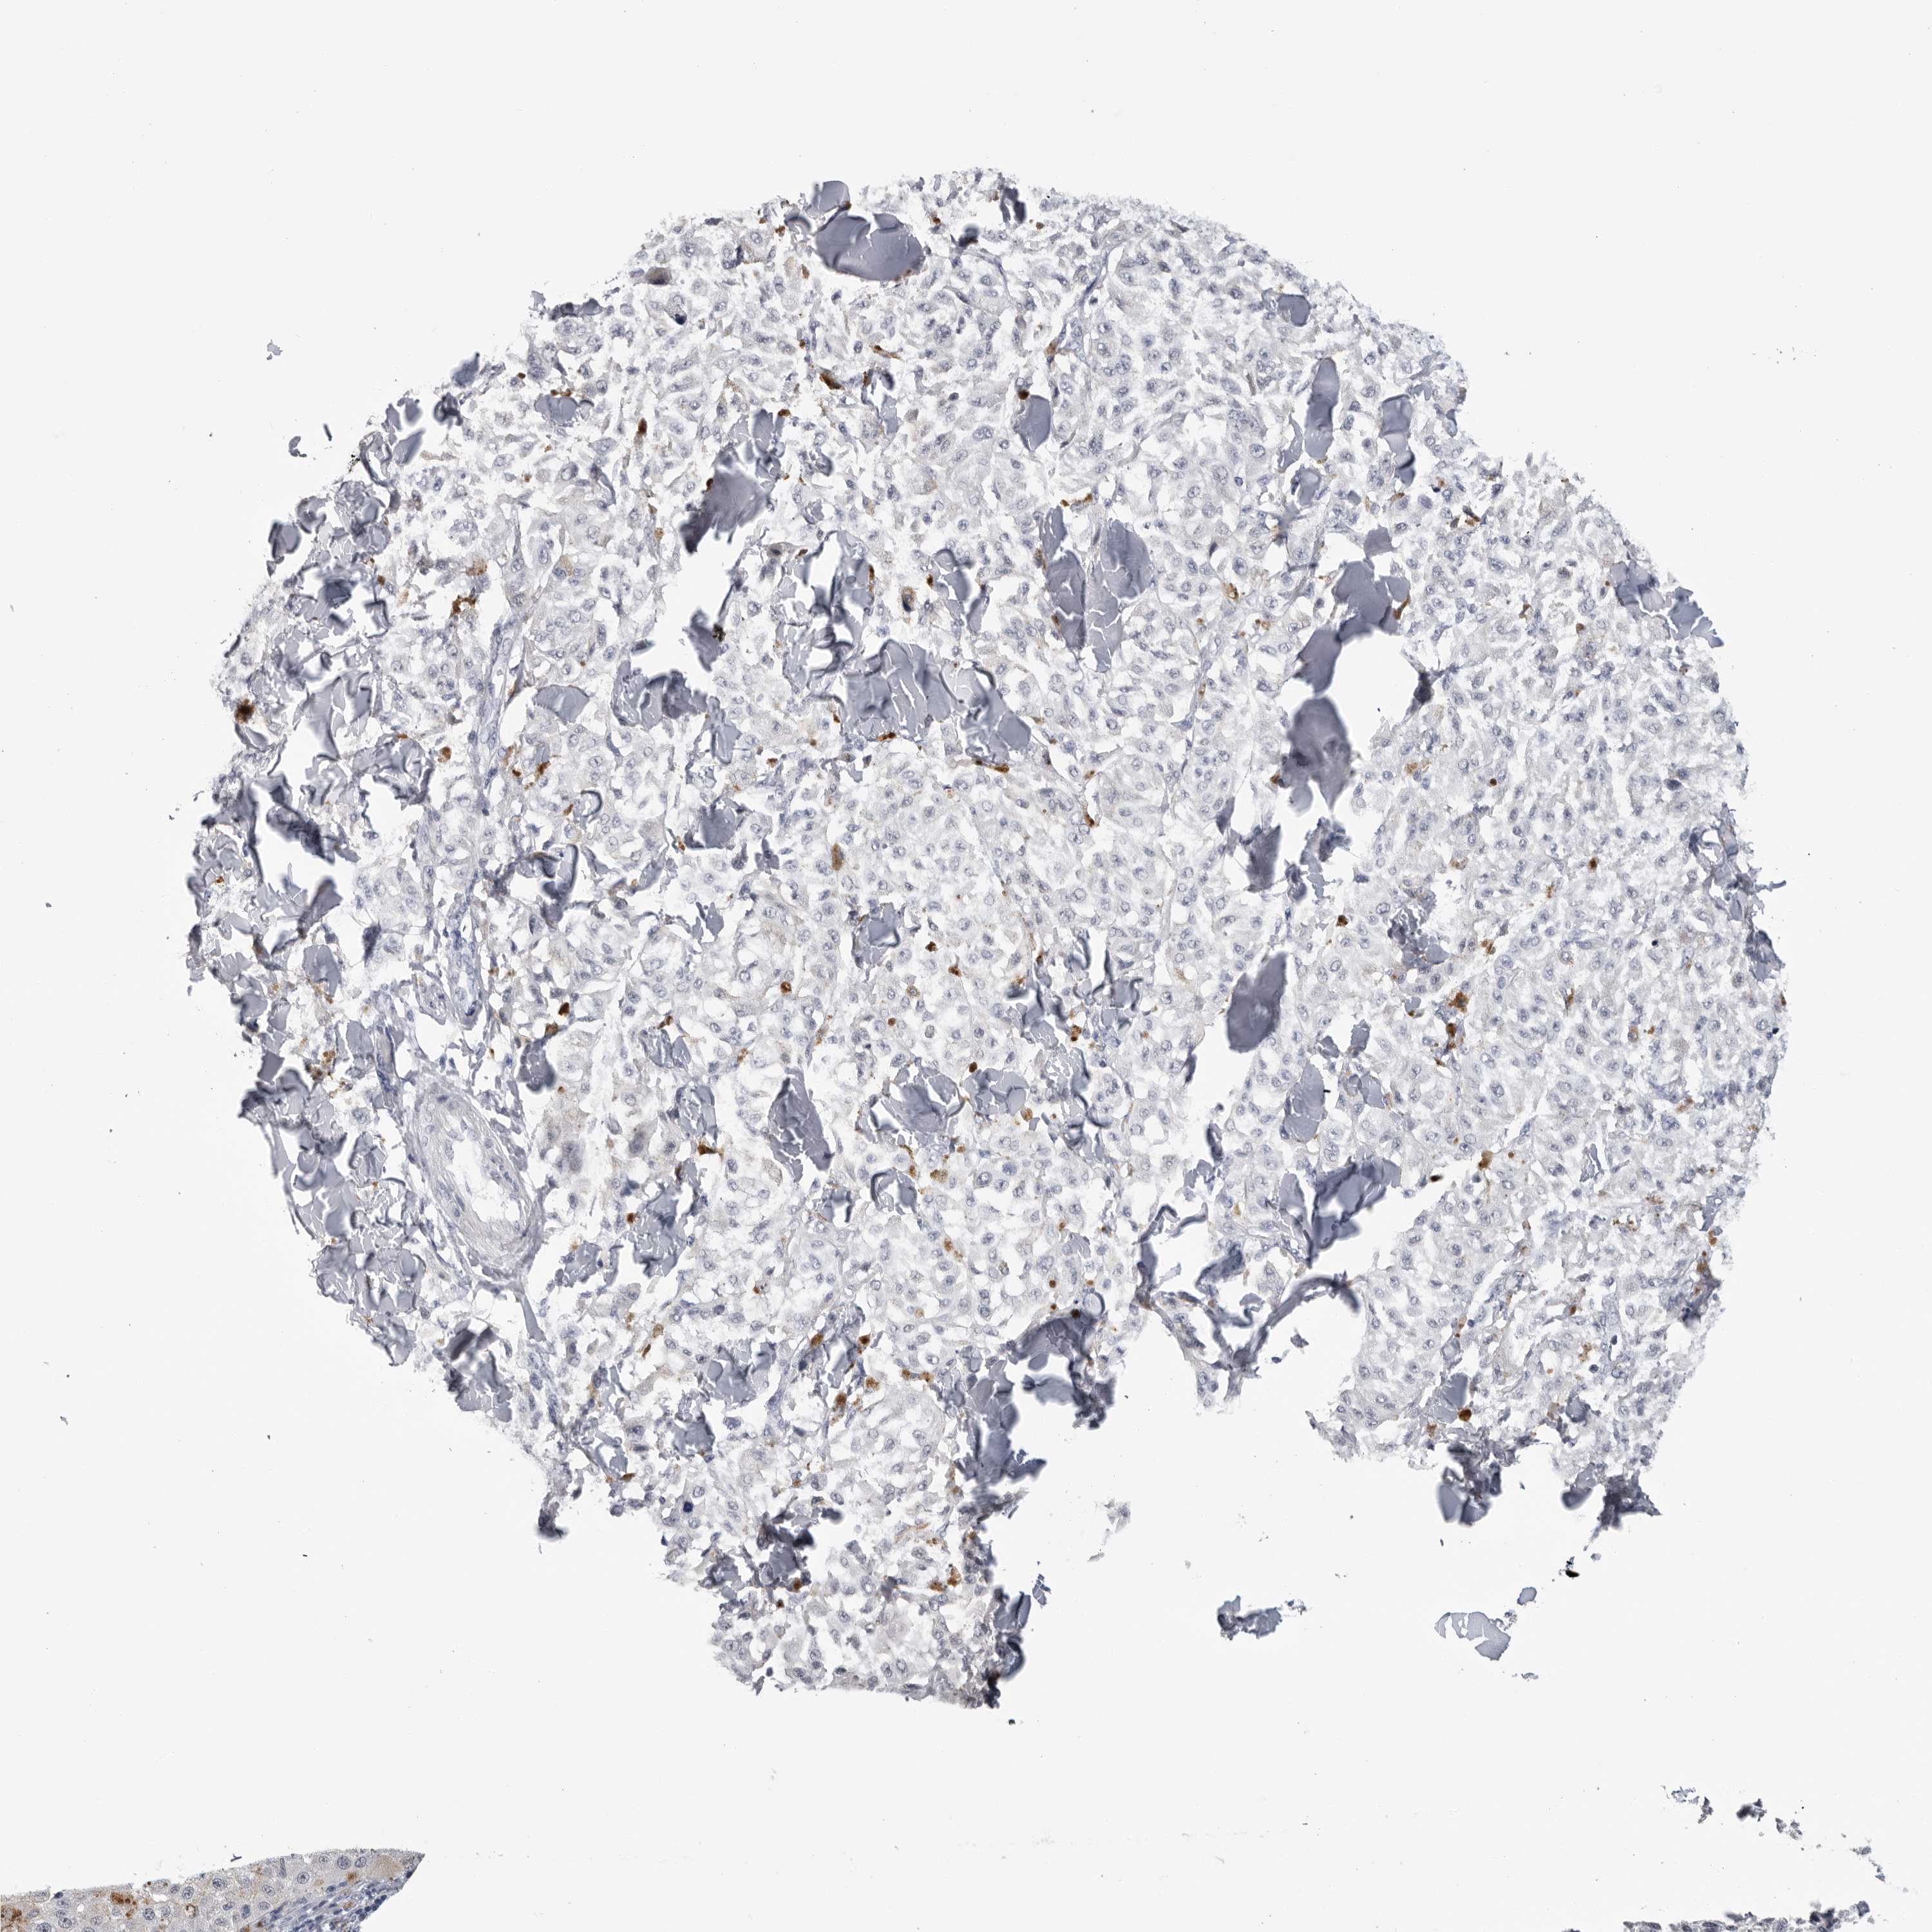

MELANOMA - Protein expressioni

A mouse-over function shows sample information and annotation data. Click on an image to view it in a full screen mode. Samples can be filtered based on level of antibody staining by selecting one or several of the following categories: high, medium, low and not detected. The assay and annotation is described here.

Note that samples used for immunohistochemistry by the Human Protein Atlas do not correspond to samples in the TCGA dataset.

Antibody stainingi

Antibody staining in the annotated cell types in the current human tissue is reported as not detected, low, medium, or high, based on conventional immunohistochemistry profiling in selected tissues. This score is based on the combination of the staining intensity and fraction of stained cells.

Each image is clickable and will lead to virtual microscopy that enables deeper exploration of all samples and also displays staining intensity scores, fraction scores and subcellular localization as well as patient and tissue information for each sample.

Antibody HPA024761

Antibody HPA029557

Staining

High

Medium

Low

Not detected

Intensity

Strong

Moderate

Weak

Negative

Quantity

>75%

75%-25%

<25%

None

Location

Nuclear

Cytoplasmic/membranous

Cytoplasmic/membranous,nuclear

Malignant melanoma, NOS

Malignant melanoma, Metastatic site